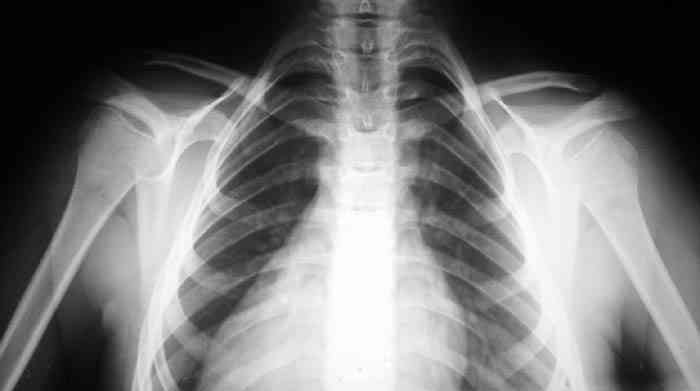

Девочка, 9 лет. Жалобы на деформацию верхнего плечевого пояса.

Объективно: приведение обоих надплечий, объем движений в плечевых суставах в полном объеме, общесоматический статус без патологии, УЗИлопаточных областей - без патологии.

Возможно речь идёт о добавочных шейных рёбрах, для уточнения целесообразно сделать боковую рентгенографию.

Больная на Вашей фотографии довольно похожа на Cleidocranial Disostosis. Пришлите снимки плечевого пояса. Это может быть недоразвитие или отсутствие ключиц.

Наличие ключиц на прямом снимке, снимает диагноз врожденного отсутствия ключиц.

Мне кажется, случай похож на Poland's Syndrom, синдром встречается при врожденной паталогии, когда отсутствует грудные мышцы (pectoralis), в большинстве случаев односторенне, и пластические хирурги рекомендует операцию.

Предлагаю пока рабочим диагнозом считать: "Врожденная аномалия грудной клетки. Добавочные шейные ребра".